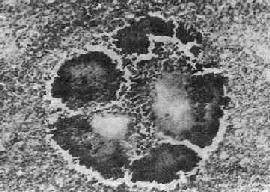

图18-36 放线菌病 病灶中的“硫黄颗粒”,周围部分菌丝排列成放线状。菌丝末端膨大呈棒状 有时组织切片中菌丝不明显,可作革兰染色,放线菌菌丝体为革兰阳性,胶样鞘为革兰阴性,据此可确诊为放线菌病。 放线菌病常同时合并其他细菌感染。病变常迁延不愈。一处病变纤维化,附近可出现新的病灶,再形成脓肿。日久后可引起大量组织破坏和瘢痕形成。颈面部放线菌病最多见,约占放线菌病总数的一半。病原菌常在口腔粘膜损伤(如拨芽等)时侵入。病变多发生在颌骨附近。早期,牙龈及邻近软组织肿胀、质硬、表面皮肤暗红色,以后液化形成脓肿。病变向周围组织扩展,形成多数脓肿,彼此沟通形成窦道,并常穿破皮肤形成瘘管。病变并可侵犯颌骨引起骨膜炎和骨髓炎,严重者可进一步扩展到颅骨、脑膜及脑。 腹内放线菌病多发生于阑尾和结肠,在粘膜下层形成小脓肿。病变常穿透肠壁引起局限性腹膜炎,并可侵入邻近肠袢、腹膜后组织和腹壁,形成排脓的窦道。有时并可通过淋巴管或血道、或直接蔓延到肝引起多发性肝脓肿,进一步可引起膈下脓肿,最后可破入胸腔引起胸腔内感染。感染也可沿腰肌蔓延到肾周围组织和腰椎,并可引起腰肌脓肿。 胸内放线菌病因吸入放线菌引起,或由腹部放线菌病蔓延而来,常形成肺脓肿,逐渐扩散可形成肺胸膜瘘或脓胸。进一步可侵犯胸壁及肋骨,引起胸壁瘘管。有时可蔓延到心包引起化脓性心包炎。